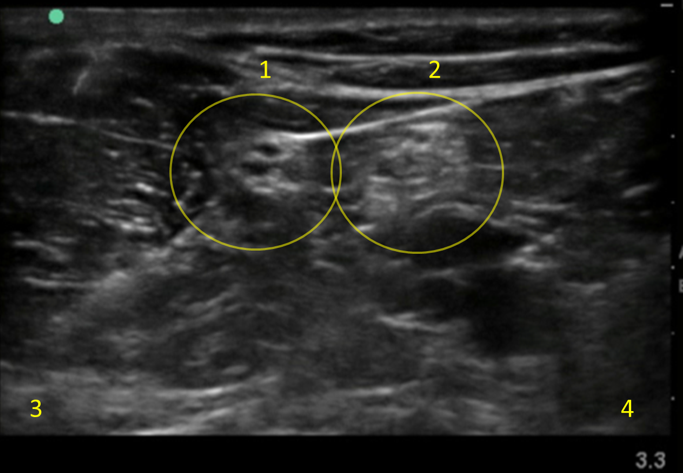

Popliteal Sciatic Nerve Block Injection 2 Image

Peroneal Nerve

Tibial Nerve

Lateral

Medial